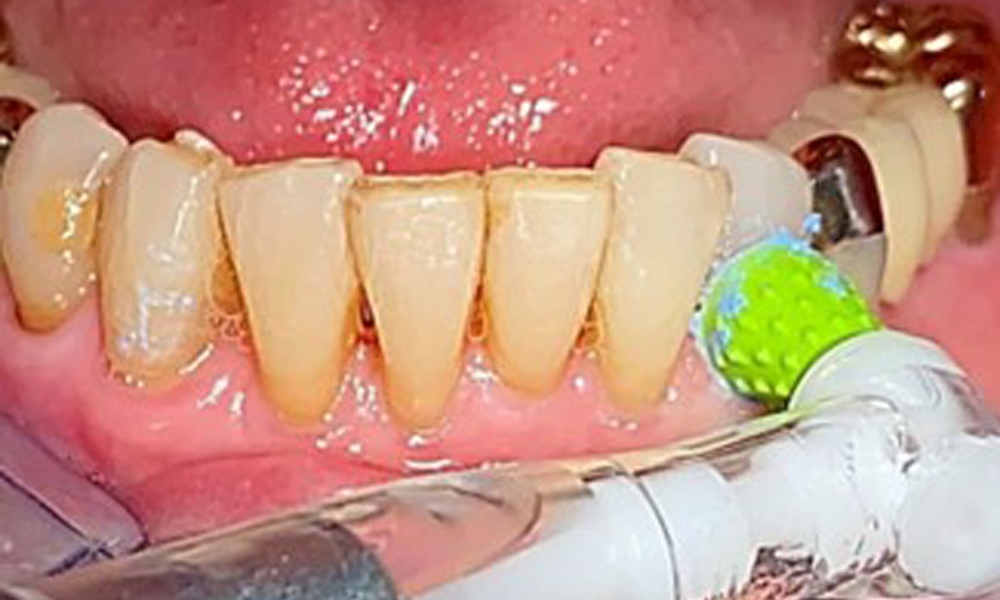

The patient was fitted with a combined removable maxillary telescopic prosthesis more than 25 years ago (Fig. 1, Fig. 2, Fig. 3) and is very happy with her dentures. The patient has an adequate fixed denture for the mandible (Fig. 4).

The dental findings are as follows: Combined removable implant and tooth-supported telescopic prostheses on implants 15, 13, 21, 23, 24, 25 and tooth 11 (Fig. 1, Fig. 2, Fig. 3). The patient was fitted with a fixed mandibular denture. Adequate bridges were present over 37 to 34 and 45 to 47 (Fig. 4), the crown margins were intact and there were no active caries. A composite filling with a marginal gap was present on tooth 43. There was mandibular gingival recession, exposing 1 to 3 mm of root surface. This also applies to 11.

An air polishing system should be used with low-abrasive powder to remove biofilm from the restoration margins, interdental areas and implant surfaces (Fig. 12). Selective polishing (Fig. 13) should be used to smooth any less sensitive areas, as this decreases bacterial reattachment (9).